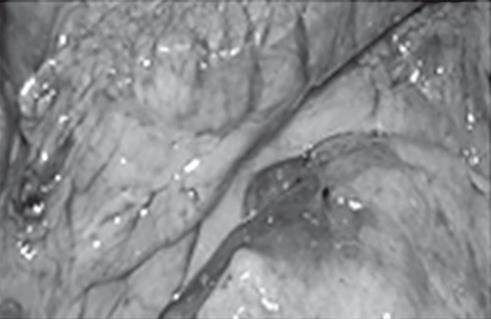

Иллюстрация к книге — Неалкогольная жировая болезнь печени [i_040.jpg]

Иллюстрация к книге — Неалкогольная жировая болезнь печени [i_041.jpg]

Хронический стеатогепатит

Иллюстрация к книге — Неалкогольная жировая болезнь печени [i_042.jpg]

Отек головного мозга

Иллюстрация к книге — Неалкогольная жировая болезнь печени [i_043.jpg]

Индуративный панкреатит

Иллюстрация к книге — Неалкогольная жировая болезнь печени [i_044.jpg]

Гипертрофия миокарда

Иллюстрация к книге — Неалкогольная жировая болезнь печени [i_045.jpg]

Минимальный левого желудочка коронарный атеросклероз

Рис. 38. Летальный случай пациентки с острым отравлением алкоголем